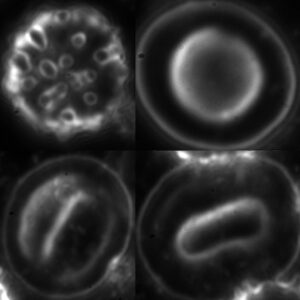

Wczesną i diagnostycznie istotną zmianą skórną jest tzw. rumień wędrujący, który zazwyczaj ma postać pierścienia z obszarami zapalnymi, zdrowymi oraz częściowo w trakcie gojenia. Może jednak przybierać nietypową, fioletowawą barwę i nie zawsze układa się w charakterystyczny pierścień. Czasami, ze względu na rozległość zmiany, jej fragmenty mogą być ukryte, np. pod włosami, co utrudnia określenie kształtu. Rumień rozwija się stopniowo, dzień po dniu.

Mimo zakażenia, rumień wędrujący nie zawsze się pojawia. Szacuje się, że jedynie w około jednej trzeciej przypadków zmiana skórna powstaje lub zostaje zauważona przez pacjenta.